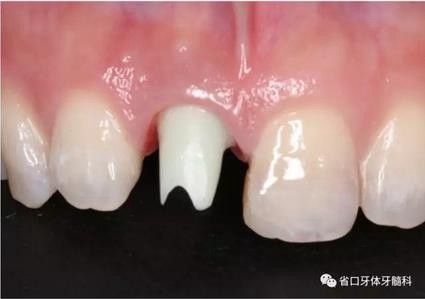

圖23 就位臨時(shí)冠

圖24 臨時(shí)冠咬合調(diào)整

(2)制備臨時(shí)冠:術(shù)后當(dāng)天取模轉(zhuǎn)移,送工廠以Zimmer®多功能 攜帶體為臨時(shí)基臺(tái)制備臨時(shí)修復(fù),獲得舌隆突開(kāi)孔螺絲固位的烤塑臨時(shí) 冠。將其就位于口內(nèi)種植體,調(diào)整正中、前伸及側(cè)方咬合無(wú)接觸,加力 10~15N·cm,可見(jiàn)即刻修復(fù)體良好地支持齦緣及牙齦乳頭結(jié)構(gòu)。